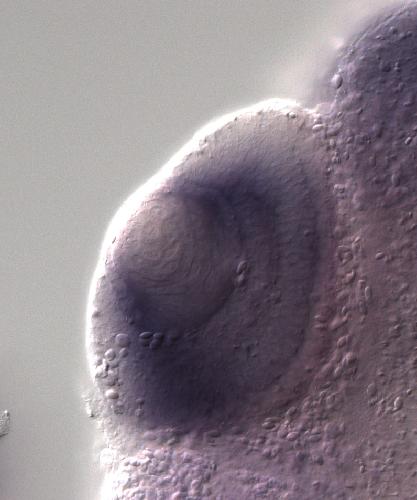

???displayGene.symbol???: trip12

???displayGene.name???: thyroid hormone receptor interactor 12

E3 ubiquitin-protein ligase involved in ubiquitin fusion degradation (UFD) pathway and regulation of DNA repair. Part of the ubiquitin fusion degradation (UFD) pathway, a process that mediates ubiquiti...[+]